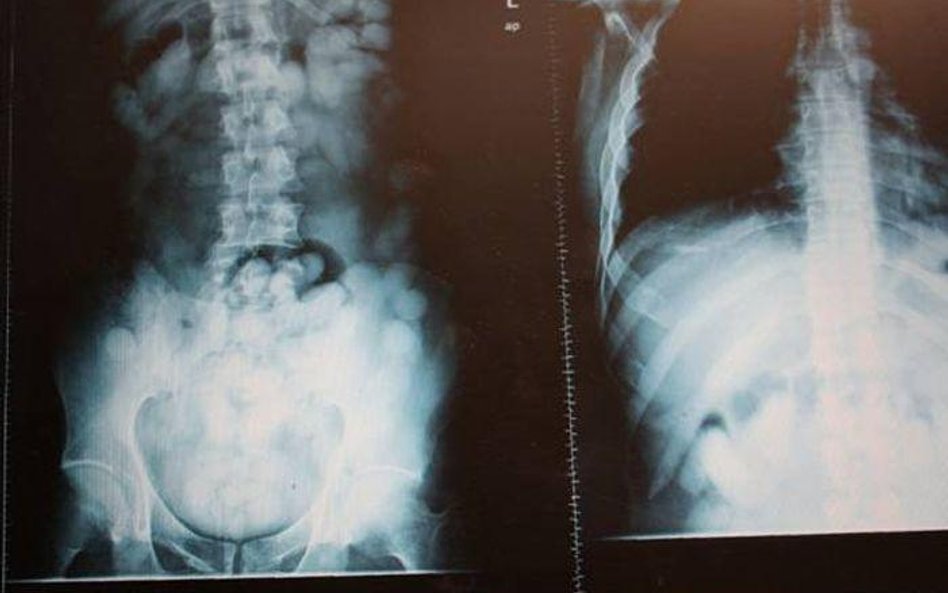

Dwa kilogramy kokainy w żołądkach

Foto: Służba Celna

Przemycana w żołądkach kokaina zapakowana była łącznie w 167 gumowych kapsułek. Wewnątrz każdej znajdowało się  od 11g do 12g. czystej kokainy. Gdyby któraś z nich pękła, groziłoby to śmiercią przemytnika, ponieważ już 1 g czystego narkotyku rozpuszczony w żołądku  to śmiertelna dawka dla człowieka.

Obaj podejrzani zostali wytypowani do kontroli na podstawie informacji uzyskanych dzięki współpracy międzynarodowej. Podejrzenie funkcjonariuszy obu służb, że podróżni przemycają narkotyk należało potwierdzić badaniami. 43 – latek odmówił poddania się badaniu moczu, a wynik badania 33 – latka wskazywał na zawartość w organizmie kokainy. Pod nadzorem funkcjonariuszy SG mężczyźni zostali przewiezieni do szpitala przy ul. Banacha na wykonanie prześwietlenia RTG, aby potwierdzić możliwość przemytu  narkotyków wewnątrz organizmu. Już w trakcie dowożenia do szpitala obaj mężczyźni przyznali się do przemytu poprzez połknięcie narkotyków w postaci kapsułek, co potwierdziło późniejsze prześwietlenie RTG.